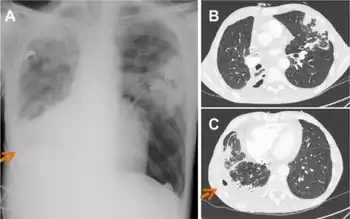

A. viscosus causes periodontal disease in animals and has been isolated from human dental calculus and root surface caries, as well as the oral cavity of hamsters and actinomycotic lesions in swine, cats, and dogs.[3][4] Furthermore, it has been shown to cause endocarditis in humans.[5] A. viscosus has also been known to cause lung infections, but only in very few cases.[1] Infections are treatable with penicillin for three-week therapies.[1]